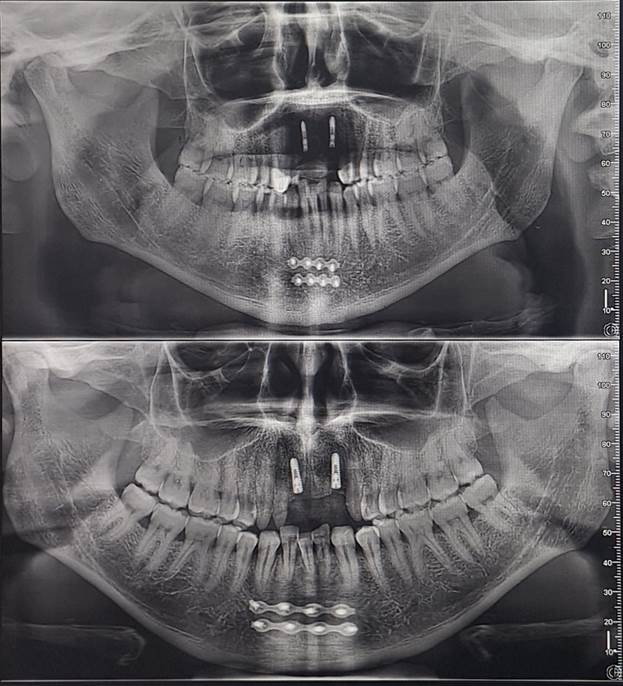

I recently received images of the damage when I got my teeth repaired and have provided them below.

Initially, I believed the damage had been repaired correctly. But over time, the injury had pulled closer together, pushing the bottom middle tooth out of alignment. I realized I would need to go to the hospital to have it broken and reset. The thought of enduring that pain again was daunting. However, when I visited DentaFly, they reassured me that the healing had gone well, and the misaligned tooth was perfectly fine and fixable. So, I requested a quote for the necessary treatment.